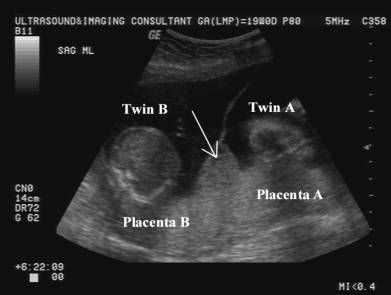

O “Sinal do Y ou λ (Lambda)” na ultrassonografia é indicativo de qual tipo de gestação Gemelar?

Dicoriônica.

No que consiste uma gestação gemelar Dicoriônica?

Placentas diferentes.